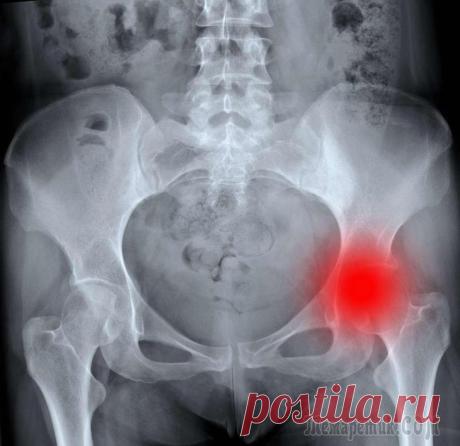

Артрит-артроз - как лечить без операции и лекарств?! Боли в суставах не только осложняют жизнь, но, как правило, свидетельствуют об опасных воспалительных и разрушительных процессах, которые постепенно сковывают движения, а при неправильном лечении или его отсутствии приводят к необратимым деформациям и инв